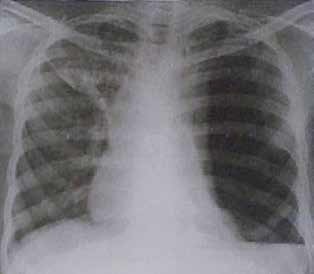

33 – Homem branco de 58 anos refere ter sido vítima de ferimento por arma branca há 2 horas. Foi atendido em Unidade Básica de Saúde onde teve seu ferimento suturado. Encontra-se hemodinamicamente estável com exame neurológico normal. O médico da UBS o encaminhou para o pronto-socorro do Hospital de referência para melhor avaliação. No PS, o paciente apresenta-se sem queixas além de dor no local da sutura. Observa-se ferimento de 2 cm no oitavo espaço intercostal esquerdo, na linha axilar média e que estava adequadamente suturado e com bom aspecto. Realizou o seguinte RX de tórax:

Nosso paciente foi vítima de ferida por arma branca em oitavo espaço intercostal esquerdo, na linha axilar média. Foi atendido inicialmente em uma Unidade Básica de Saúde, onde teve sua ferida suturada, e em seguida encaminhado ao pronto-socorro para avaliação. Exceto por dor local, encontra-se assintomático e hemodinamicamente

estável. Foi realizada radiografia de tórax, com presença de pneumotórax à esquerda, atelectasia total do pulmão esquerdo e desvio do mediastino para a direita. Com este desvio, o pneumotórax não deve ser considerado simples. Contudo, faltam manifestações clínicas para afirmarmos que este é hipertensivo, uma vez que o diagnóstico de pneumotórax hipertensivo é clínico. Agora, é

improvável que um indivíduo com uma radiografia como esta não tenha uma ou mais evidências clínicas de um pneumotórax hipertensivo, como hipotensão, turgência jugular, cianose, taquipneia etc. Sabemos também que o fechamento de uma ferida torácica é condição que pode levar a um pneumotórax hipertensivo. Foi, no mínimo, infeliz a escolha dessa radiografia para a questão. Há presença de nível líquido, o que deve ser imediatamente diagnosticado como um hemotórax.

32 – Homem branco de 58 anos refere ter sido vítima de ferimento por arma branca há 2 horas. Foi atenatendido em Unidade Básica de Saúde onde teve seu ferimento suturado. Encontra-se hemodinamicamente estável com exame neurológico normal. O médico da UBS o encaminhou para o pronto-socorro do hospital de referência para melhor avaliação. No PS, o paciente apresenta-se sem queixas além de dor no local

da sutura. Observa-se ferimento de 2 cm no oitavo espaço intercostal esquerdo, na linha axilar média e que estava adequadamente suturado e com bom aspecto. Realizou o seguinte RX de tórax:

Vítima de ferida por arma branca em oitavo espaço intercostal esquerdo, na linha axilar média, nosso paciente teve sua lesão suturada em uma Unidade Básica de Saúde. Foi encaminhado ao pronto-socorro para avaliação. De acordo com o enunciado, está assintomático. Foi realizada radiografia de tórax. O que identificamos na imagem? Bom, de início observamos um importante pneumotórax (setas amarelas), com atelectasia de todo o pulmão esquerdo. Há desvio da traqueia também. Podemos dizer que pelo desvio do

mediastino apresentado, este pneumotórax não pode ser considerado simples. Por outro lado, o diagnóstico de um pneumotórax hipertensivo é clínico. Mas, cá entre nós, com esse achado radiológico certamente deveríamos ter uma ou mais manifestações de pneumotórax hipertensivo, tais como, hipotensão, turgência jugular, taquipneia, cianose etc. Além disso, o fechamento completo de uma ferida torácica é condição que predispõe ao pneumotórax hipertensivo. Concluímos que o autor foi extremamente infeliz na escolha dessa imagem para o enunciado, uma vez que o paciente não

apresenta sintomas. Estamos lidando com uma “dissociação enunciado-radiológica”. Vamos continuar nossa análise. Além do pneumotórax, existe franco velamento do seio costofrênico esquerdo, o que representa um derrame pleural (seta azul). Sabemos que no trauma, todo o derrame pleural deve ser obrigatoriamente encarado como um hemotórax. Sendo assim, os principais achados radiológicos são de hemopneumotórax à esquerda e desvio do mediastino para a direita.